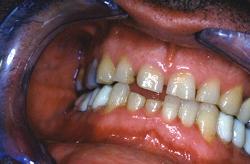

Couronnes tout céramique. Présentation d’un cas clinique : Patient d'une quarantaine d'année bruxomane, présentant des douleurs cervicales et des céphalées matinales. Il existe aussi une perte de la dimension verticale d'occlusion.

Patient d'une quarantaine d'année bruxomane, présentant des douleurs cervicales et des céphalées matinales.

Il existe aussi une perte de la dimension verticale d'occlusion.

Absence de visibilité des dents supérieures lors du sourire forcé

Vue intra-buccale en occlusion

L'espace de repos est très important. La lèvre supérieure est tombante